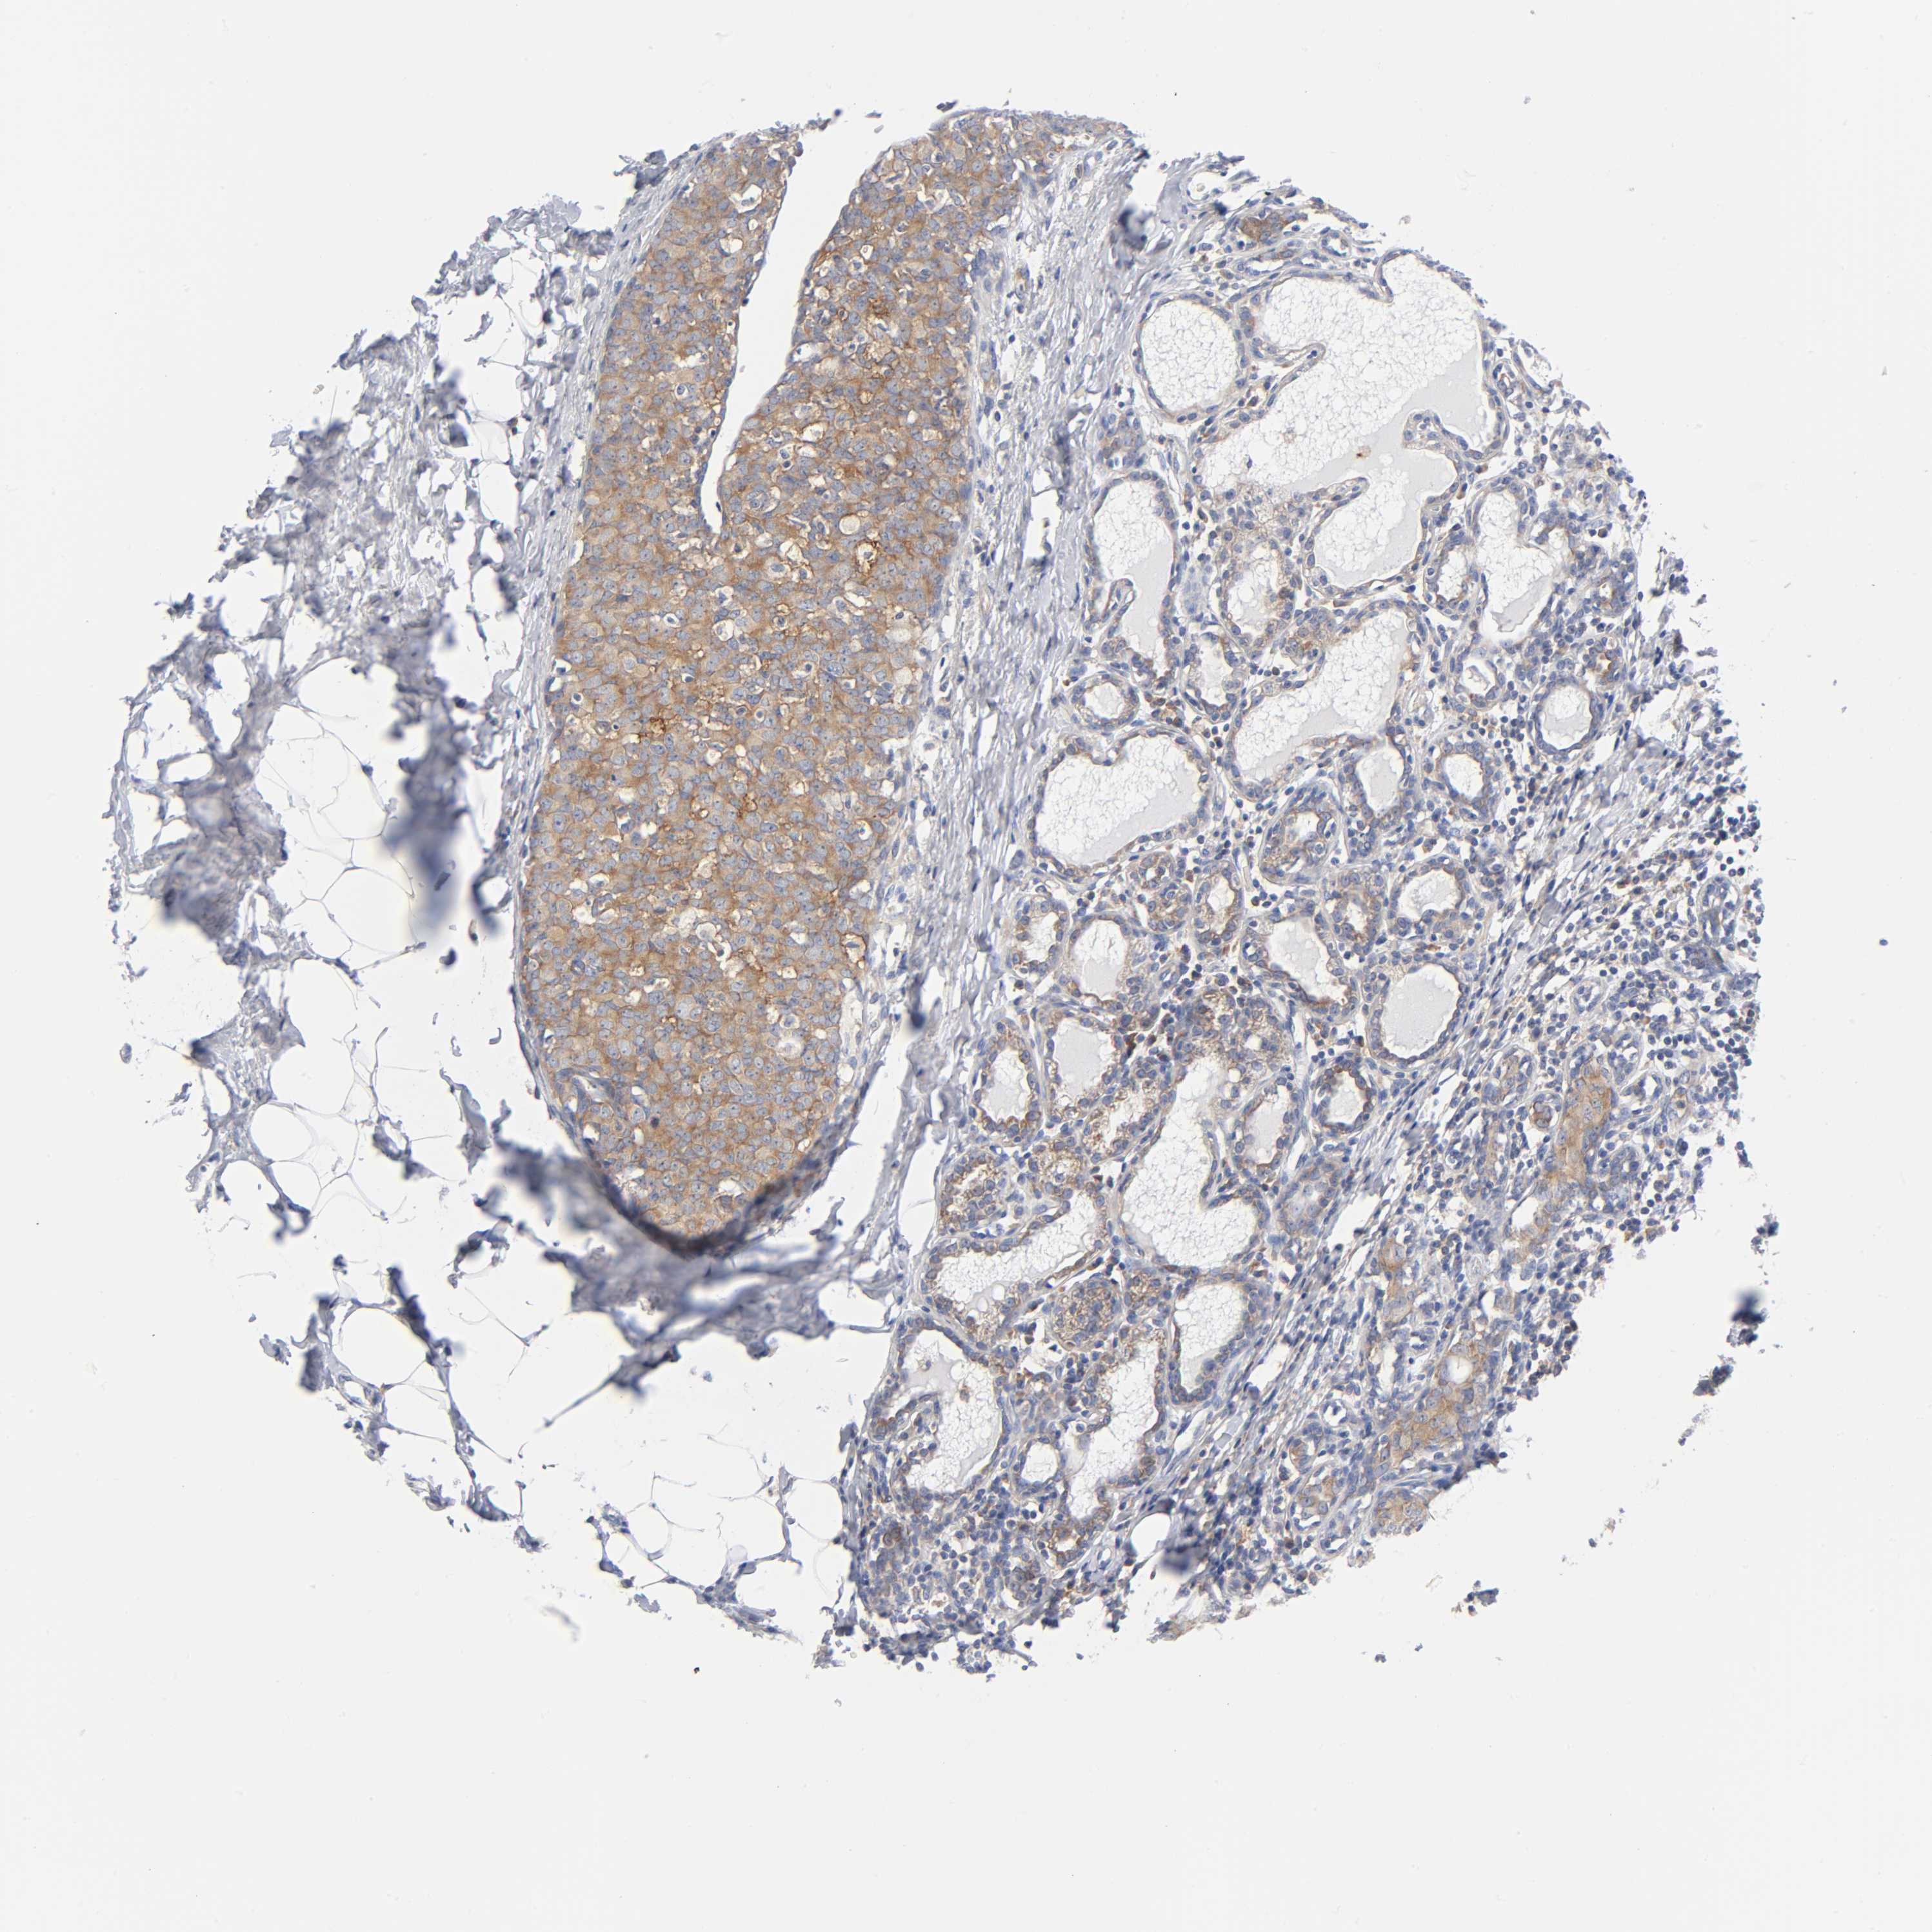

CANCER BREAST CANCER Show tissue menu

Breast cancer

Human cancer